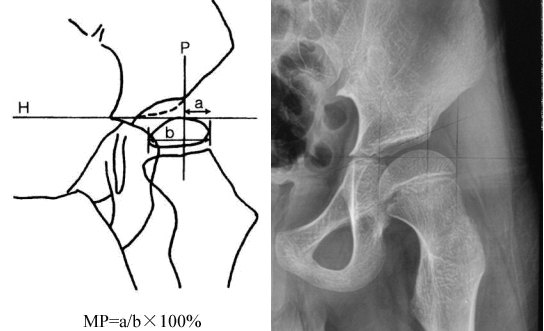

脑瘫患儿继发性髋关节发育异常的x线检测 - 好大夫在线

a:术前ce角=18°,ac角=20°,sharps角=44